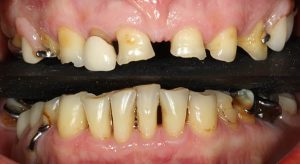

Teeth can be repeatedly filled when broken, with bigger and...

Read More +Replacing failing teeth